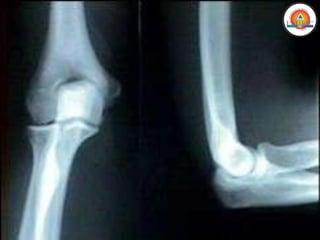

Flexión/Extensión

• Ocurren en el plano

sagital

• Flexión: ↓del ángulo

entre dos segmentos

corporales

• Extensión: ↑ del ángulo

Flexión/Extensión • Ocurren enel plano sagital • Flexión: ↓del ángulo entre dos segmentos corporales • Extensión: ↑ del ángulo entre dos segmentos corporales